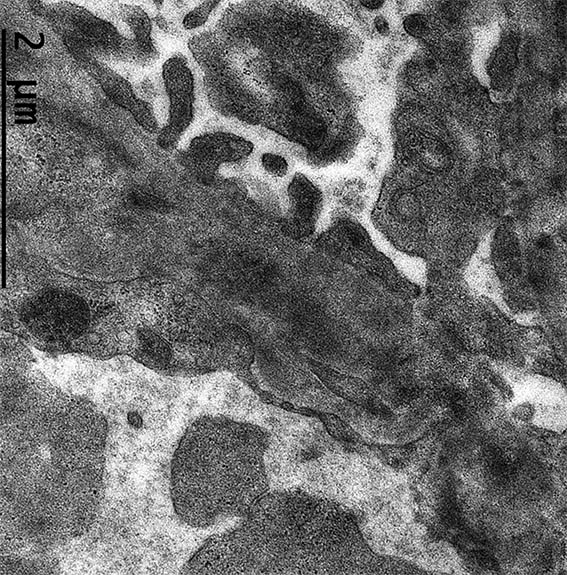

Figura 11. Microscopía electrónica, aumento original: X2.500. Hay edema endotelial y depósitos electron-densos subendoteliales.

Figura 12. Microscopía electrónica, aumento original: X4.000. Engrosamiento irregular de la MBG y depósitos electron-densos subendoteliales.

Figura 13. Microscopía electrónica, aumento original: X4.000. Depósitos electron-densos no organizados subendoteliales. Endotelio con pérdida de las fenestraciones por edema.

Figura 14. Microscopía electrónica, aumento original: X4.000.